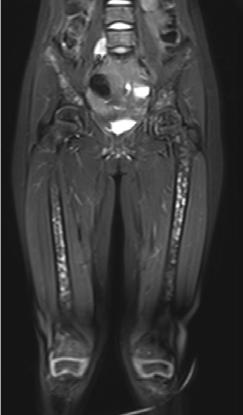

Femenino de 7 años con diagnóstico de Neuroblastoma, se realiza PET/RM con [18F]F-DOPA para estadiaje, con evidencia de lesión primaria a nivel de retroperitoneo y conglomerados locoregionales así como infiltración a médula ósea del esqueleto axial y apendicular (Figura 1A), posteriormente la paciente fue tratada quirúrgicamente con resección de la lesión primaria así como tratamiento con inmunoterapia y transplante autólogo de médula ósea además de radioterapia. Al presentar refractariedad al tratamiento comentado, se plantea la posibilidad de administrar Lutecio (177Lu) oxodotreotide, por lo que se sugiere realizar PET/RM con [18F]Octreotide para valorar expresión de receptores de somatostatina y considerar la terapia con radionúclidos para receptores de péptidos (PRRT), el estudio muestra evidencia de sobreexpresión anormal de dichos receptores en retroperitoneo, espacio subpleural izquierdo además de esqueleto axial y apendicular (Figura 1B).

Estudio PET con 6-[18F]DOPA 3A) y [18F]OCTREOTIDE 3B) en cortes coronales de secuencias T2 de miembros pélvicos y con imágenes fusionadas, donde se identifica mayor sobreexpresión anormal de los receptores de somatostatina al compararlos con 6-[18F]DOPA, y que hace candidata a la paciente para PRRT.